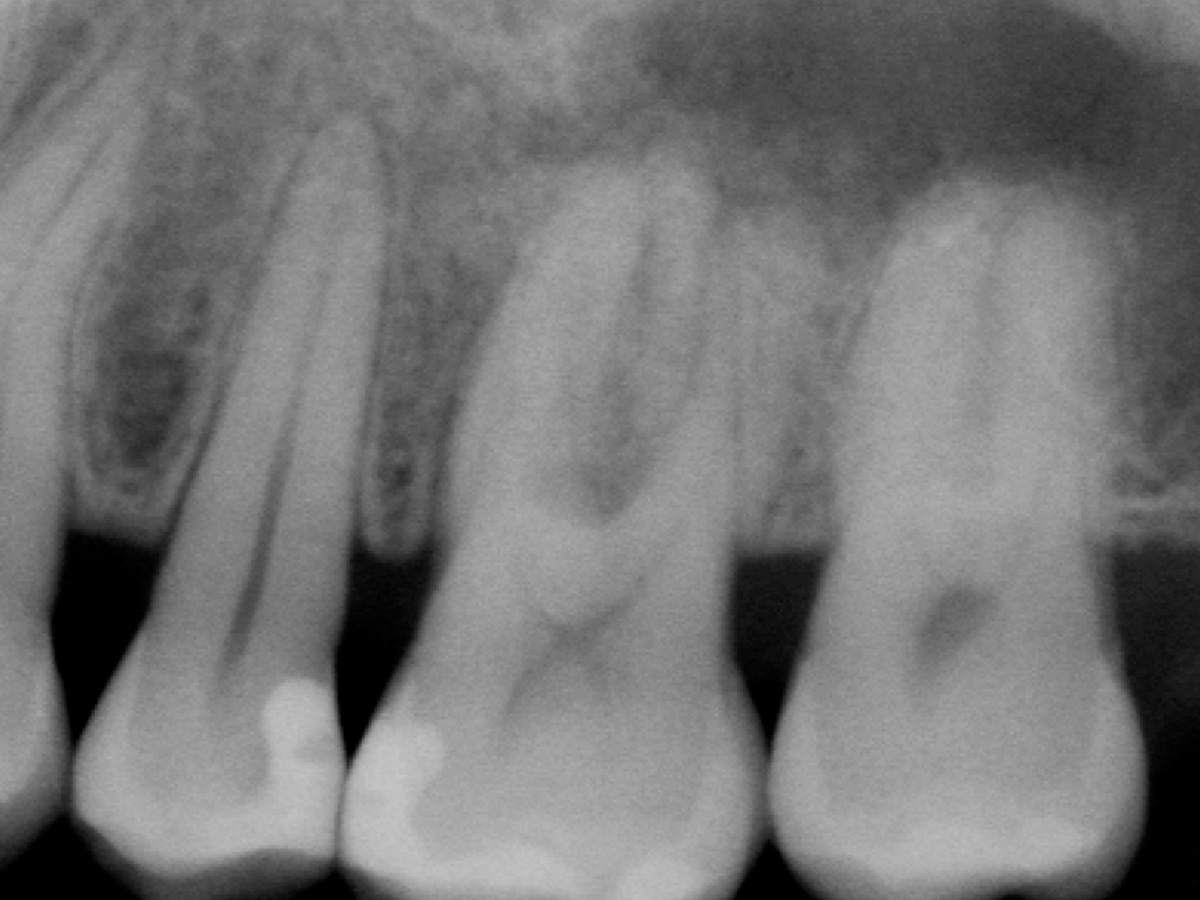

Abbildung 2

Röntgenologische Ausgangssituation Zahn 26: Komplexer parodontaler Knochenabbau im Furkationsbereich sowie periapikal der mesiobukkalen Wurzel.

Abbildung 10

Röntgen-Kontrolle nach drei Monaten: Komplette Auffüllung des parodontalen Defektes.